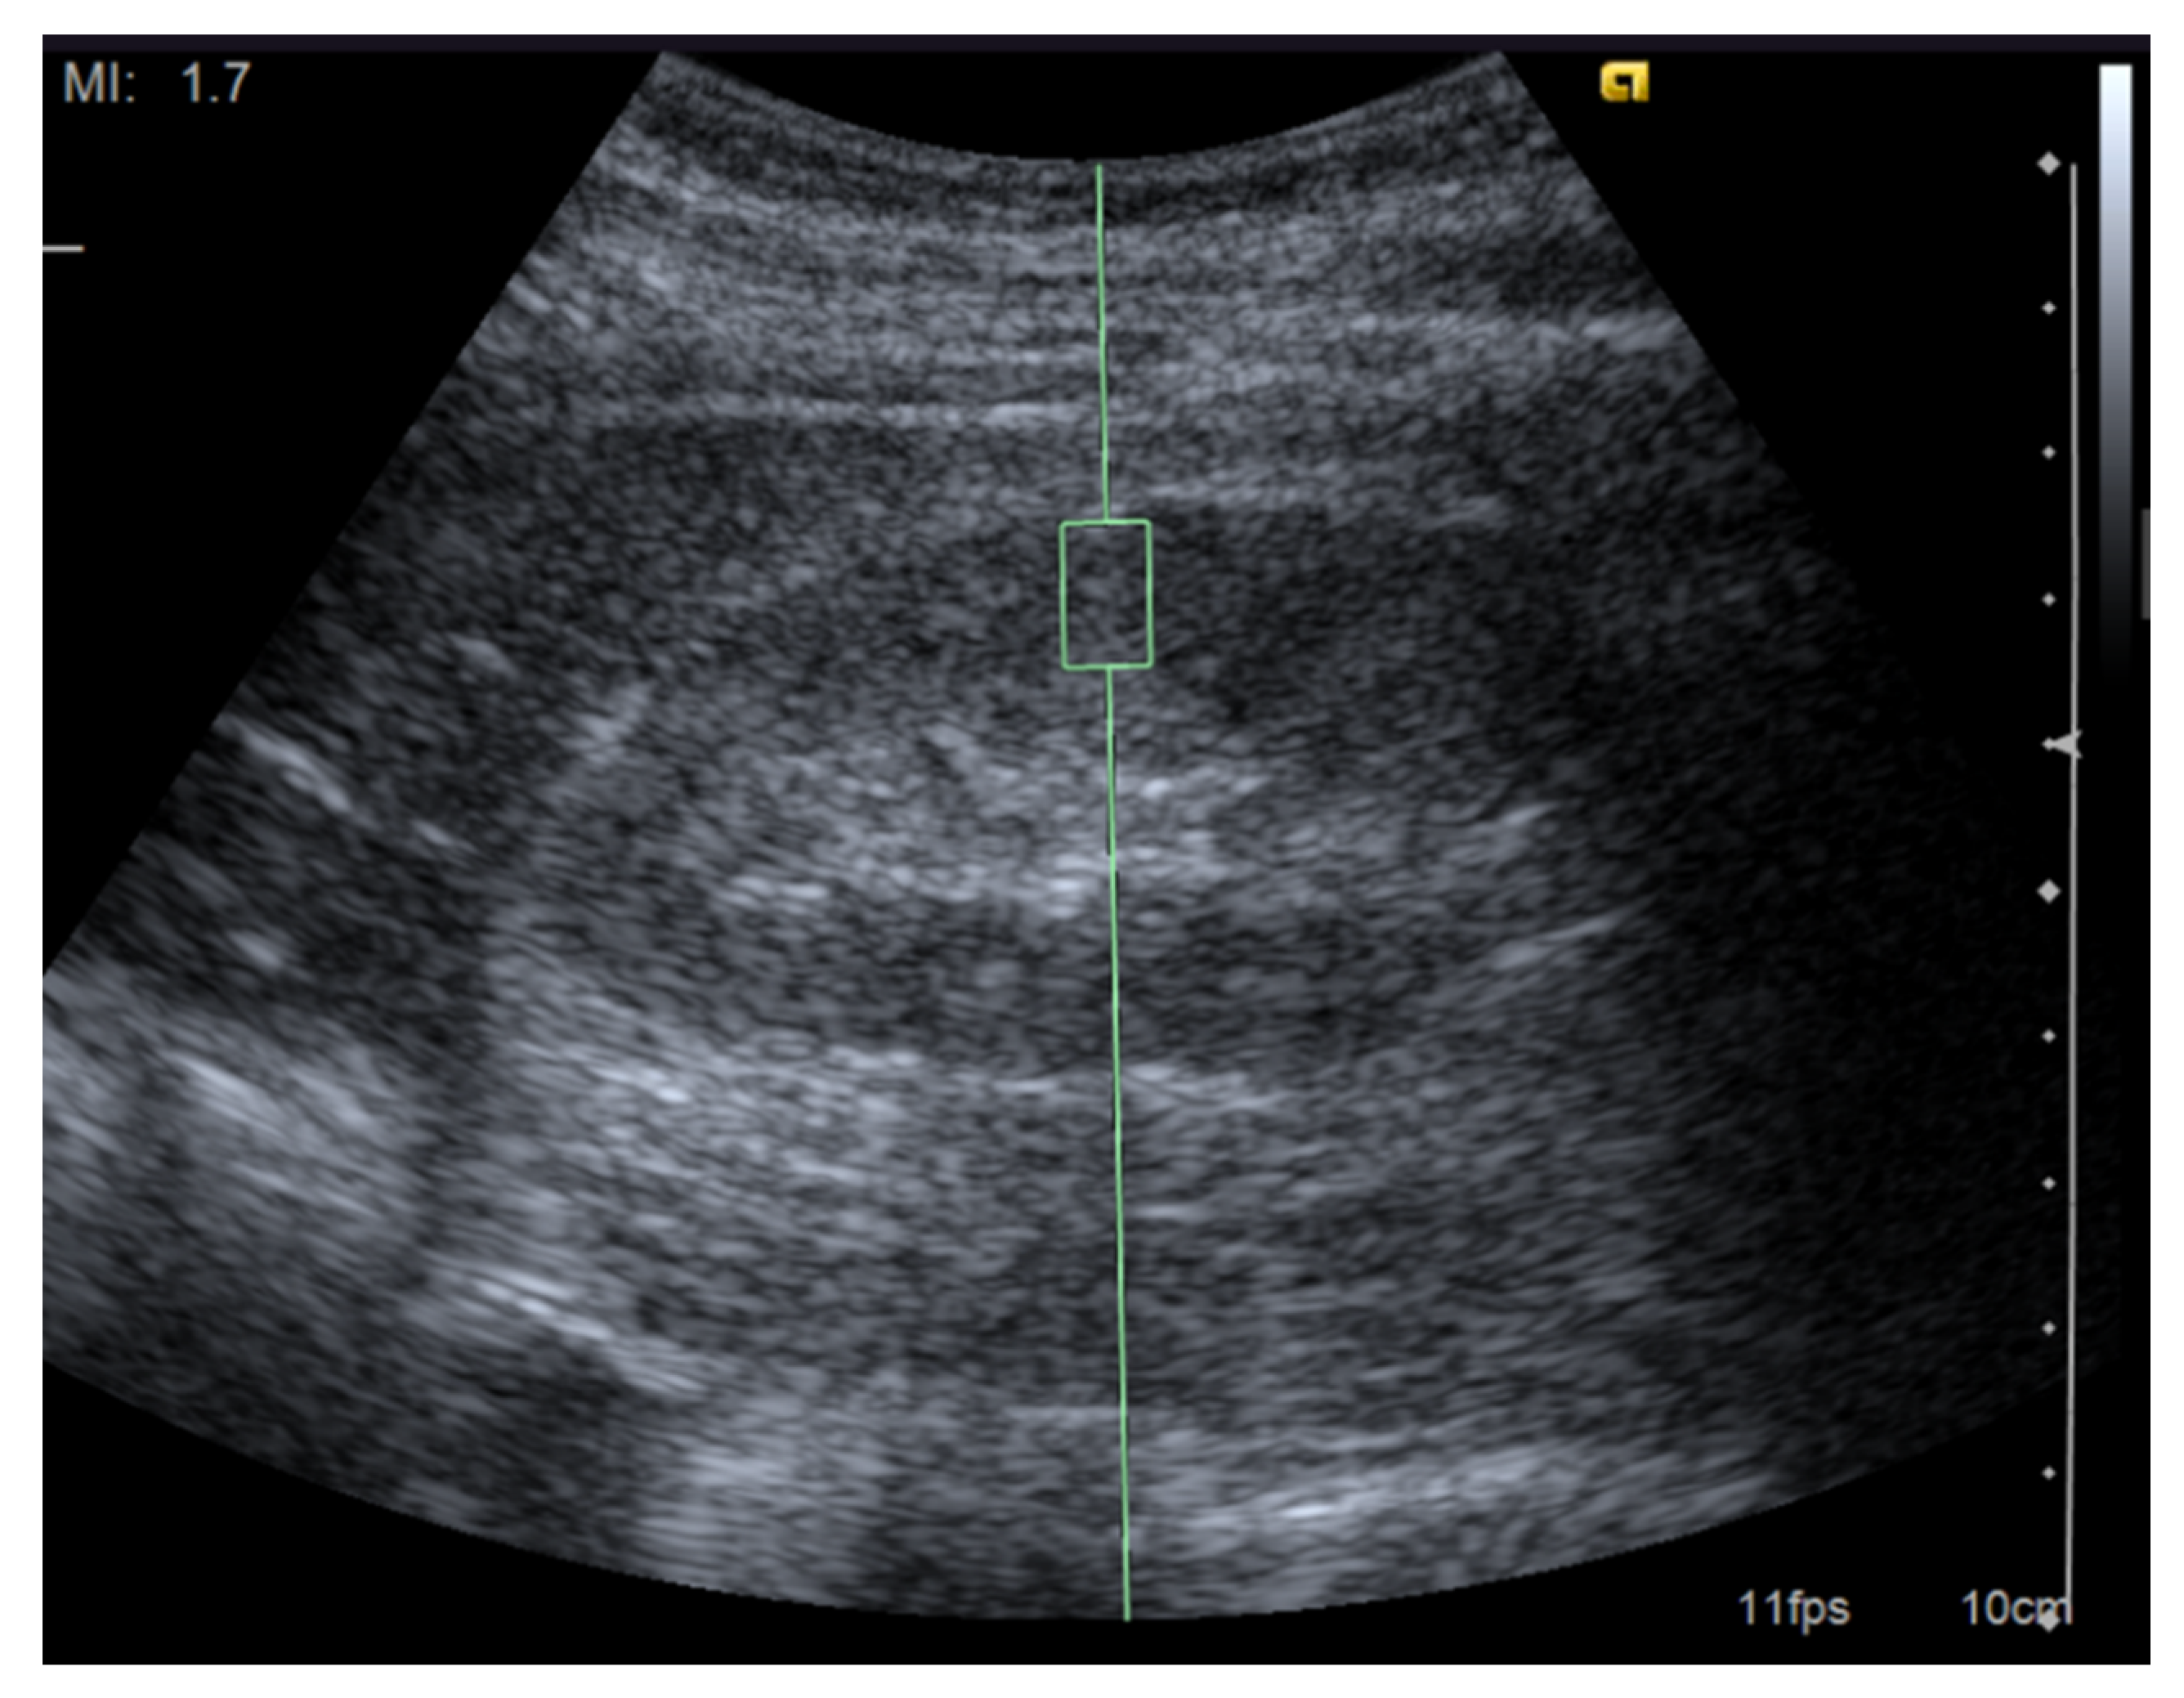

First, the target ROI must be carefully selected (Figure 1). Bob et al. investigated the potential factors influencing the results of the ARFI measurements. The depth of the ROI affects the SWV [23,24]. The push-pulse to induce shear waves tends to attenuate in deeply located tissues; thus, the elastography values correlate negatively with the depth of the ROI. Therefore, in contrast with the superficial organs such as the breast and thyroid, the depth of the ROI should be matched to the best extent. For this reason, it is preferable to perform SWE of the kidney with the patients placed in prone or unilateral positions. Most previous reports set the ROI at the renal cortex or parenchyma. It has been suggested that the measurement in the cortex is more reliable than in the medulla [25]. In patients with an impaired renal function, the kidneys show atrophic changes. The shortening of the kidney length and lessening of the parenchymal thickness in advanced kidney disease are widely recognized changes often observed by an abdominal ultrasound [26,27]. Although a careful determination of the ROI is required, the SWV can be measured reproducibly even in a patient with end-stage renal disease with a thin parenchymal thickness [28].

Figure 1.

Image of a shear wave elastography measurement. Representative ultrasound image for the measurement of renal elasticity using a Siemens Acuson S2000 ultrasound system (Siemens, Erlangen, Germany) with convex probes (4C1, frequency range: 1–4 MHz) and a mechanical index of 1.7. The region of interest was set perpendicular to the renal capsule.